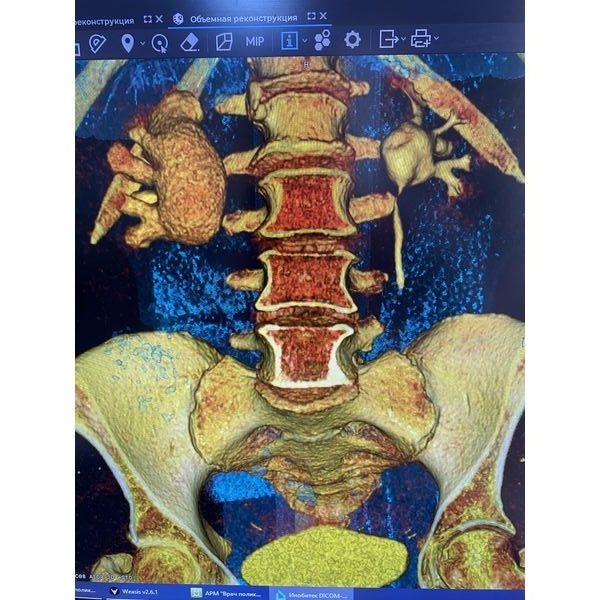

Компьютерная томография (КТ) почек и мочевыводящих путей с контрастированием обнаружила:

- камень в лоханке правой почки, размер — 10,5 × 15,6 мм, плотность — до 1853 HU;

- функциональная способность обеих почек — в норме (они выделяли контрастное вещество);

полостные элементы правой почки — расширены (вероятно, за счёт сужения в лоханочно-мочеточниковом сегменте);

- правый мочеточник — не контрастирован.